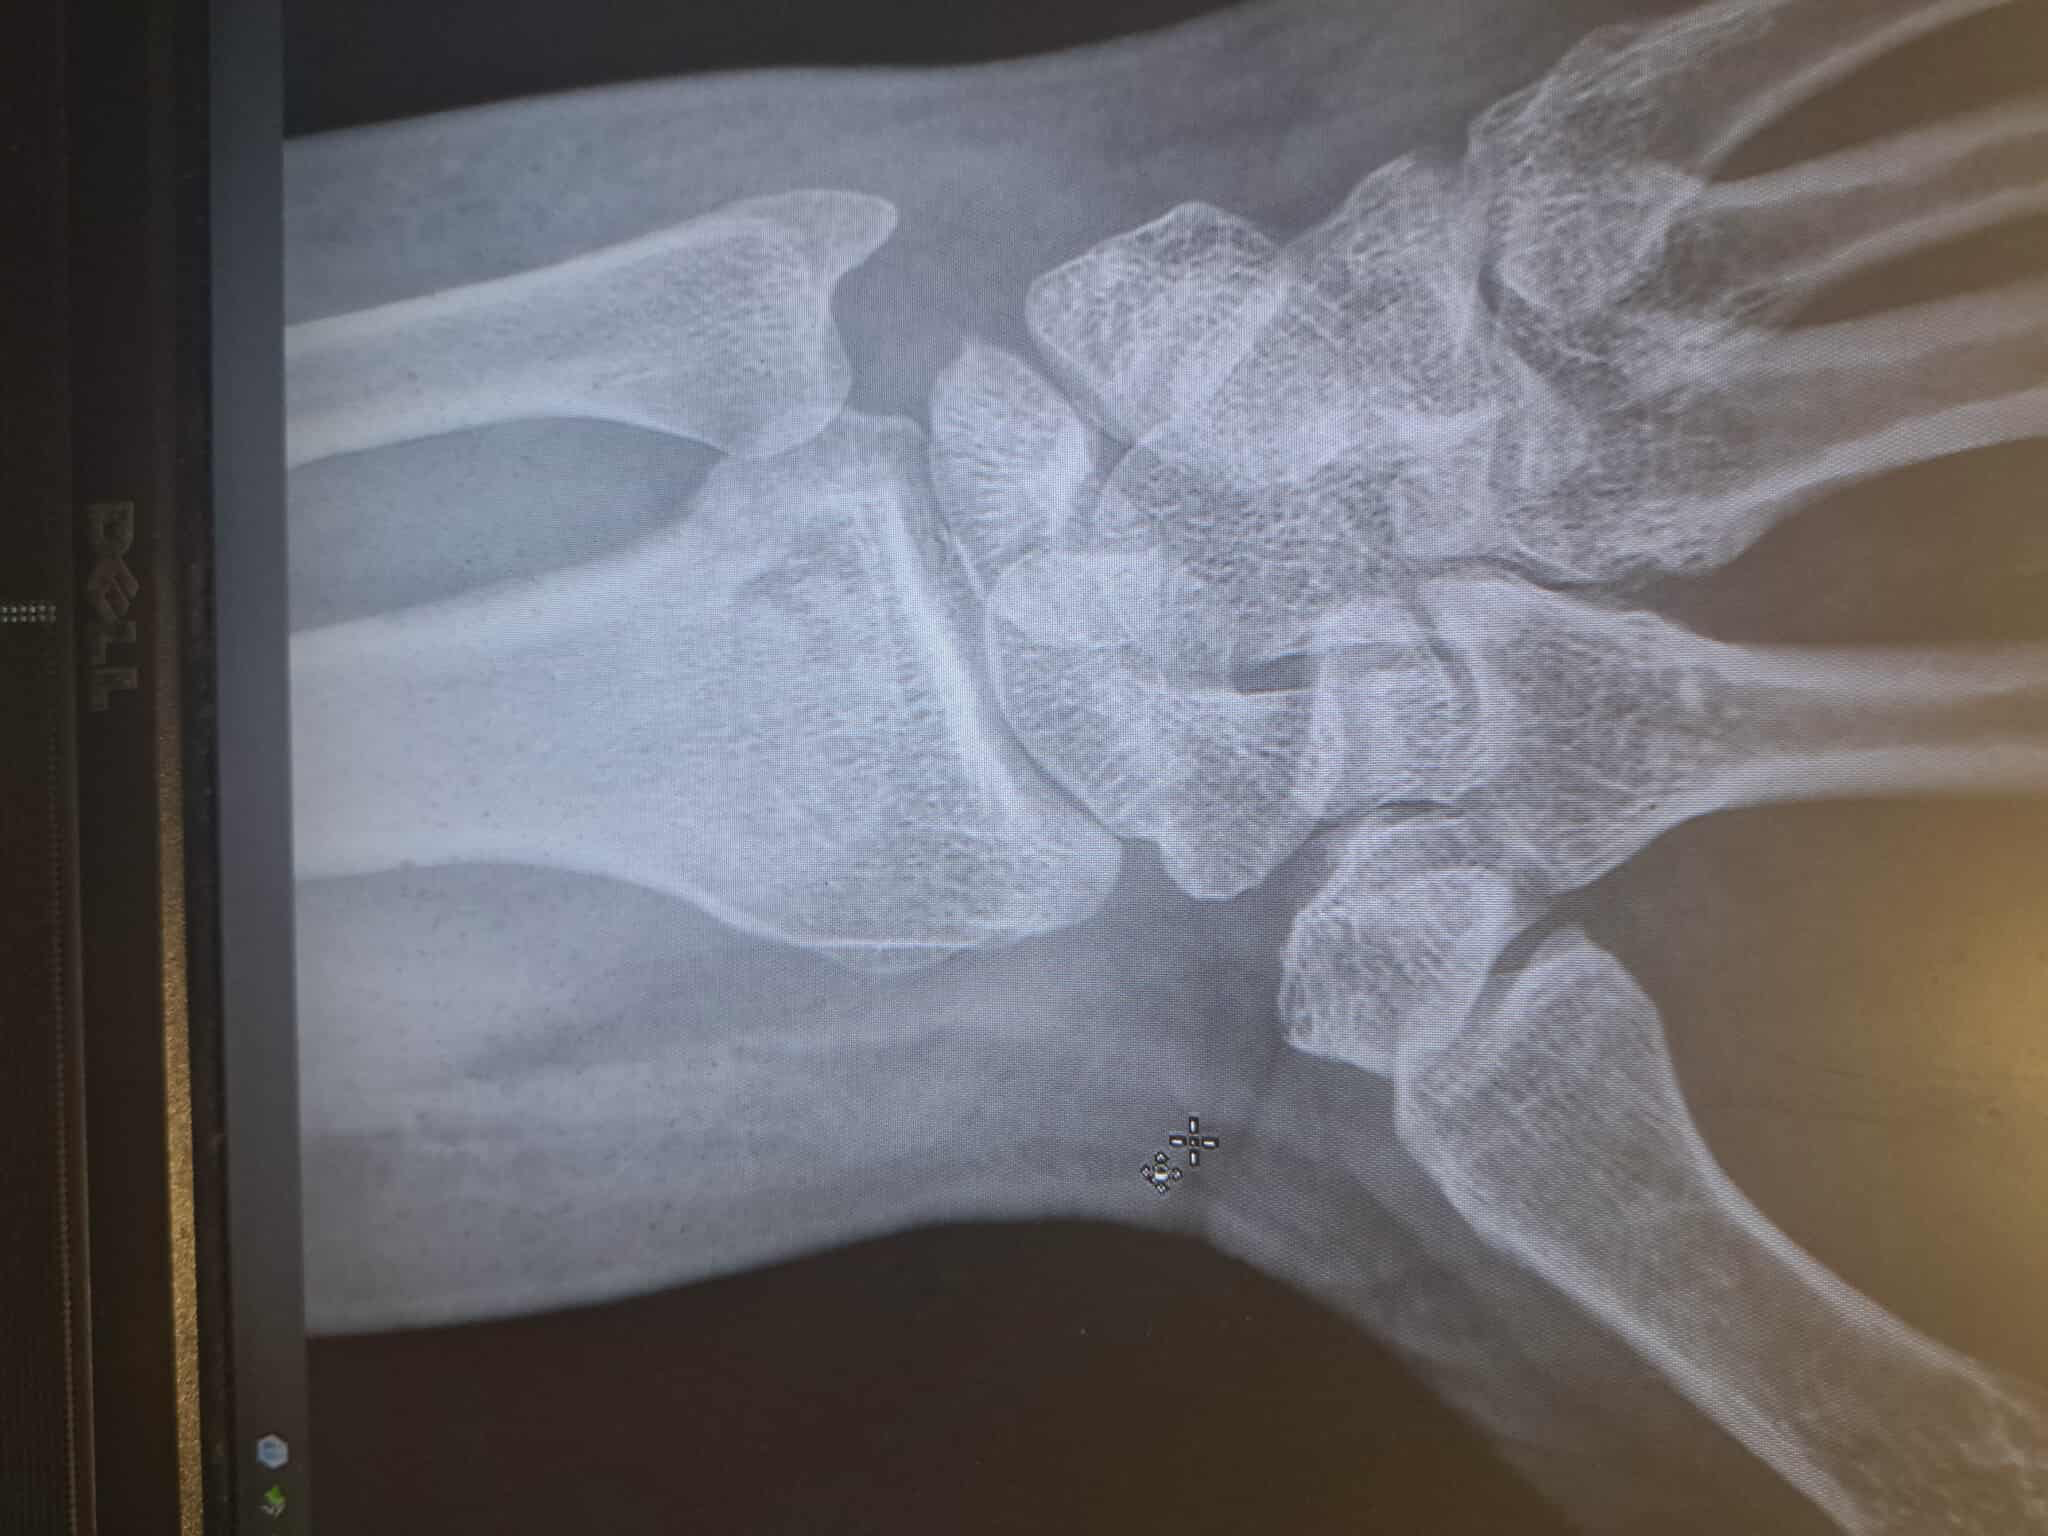

Jody's most critical injuries were having his left wrist broken, as well as blunt force trauma, contusions, and serious 'road burn' to his right arm—which could result in nerve damage. He has limited use of both arms and almost no abilities with his left hand at all.